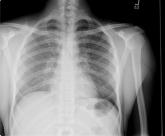

ArticleDisseminated histoplasmosisAuthor:Mark C. Henderson, MD, FACPPublish date: February 12, 2007Read More